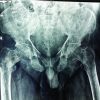

A 72-year-old female with a history of long-standing diabetes presented with fatigue, fever, and rashes on the upper limbs for 1 week. She denied any history of weight loss or loss of appetite. On physical examination, she exhibited no signs of distress, cyanosis, clubbing, raised jugular venous pressure, pedal edema, or lymphadenopathy. Her chest wall and spine were non-tender on palpation, and examinations of the abdominal, cardiovascular, pulmonary, and neurological systems were unremarkable. Laboratory investigations showed anemia (Hemoglobin: 6.4 g/dL) and severe thrombocytopenia (platelet count: 6000/μL) with a leukoerythroblastic blood picture on peripheral smear. Computed tomography (CT) scans of the abdomen and chest were unrevealing. Bone marrow aspiration and biopsy showed marrow spaces completely replaced by proliferating thin-walled vessels. In certain areas, clusters of plump spindle cells, likely endothelial cells, were observed. Immunohistochemical staining demonstrated that both the vessels and the spindle cells were strongly positive for CD31 and CD34, all suggestive of vascular neoplasia (Fig. 1). However, further positron emission tomography (PET) scan investigation revealed multiple non-avid lytic areas involving almost the entire visualized skeleton, suggestive of skeletal angiomatosis, and non-avid cystic lesions in the liver indicative of visceral angiomatosis, leading to the diagnosis of systemic cystic angiomatosis (Fig. 2-5).

Systemic cystic angiomatosis (SCA) is a rare disorder with multisystemic vascular involvement of the skeletal system and other organ systems, such as the spleen, liver, and lungs. Classically, in the bones, SCA represents a maldeveloped vascular and/or lymphatic system, characterized by multifocal bony cysts with a honeycombed or “bubble” appearance, without aggressive osteolysis with neither peripheral soft-tissue involvement nor a periosteal reaction [1]. Najm et al. conducted a comprehensive review of the existing literature, identifying a total of 48 patients across 36 case reports, which includes their own 4 cases [2]. The mean age at presentation was 22 years; however, there appears to be a bimodal distribution due to cases presenting later in life [2-5]. It is noted that males are more frequently affected than females [6]. The etiology of solitary congenital absence (SCA) remains unclear, but it is believed to result from abnormalities in vascular and/or lymphatic development [7]. The clinical presentation of SCA varies significantly. Most cases involve bony cysts, predominantly affecting the femur and pelvic bones [8,9]. Spinal involvement is observed in up to 50% of patients [10], while less commonly, it can affect the small bones of the hands [11]. Visceral involvement occurs in approximately 35% of reported cases, with the spleen being the most commonly affected organ, noted in a quarter of cases [2]. Other affected sites include the skin, soft tissues, thymus, liver, kidneys, mediastinum, and mesentery. The lung and pleural involvement are rare [11]. Complications associated with SCA include bony pain, pathological fractures, deformities, splenic rupture, chylothorax, and spinal cord compression [2,6,12]. Alkaline phosphatase levels have been reported as elevated in some cases due to extensive lytic osseous lesions, although in many reports, they were within normal limits [13]. Currently, there is no confirmed treatment for SCA. However, spontaneous regression leading to cure has been reported in some cases [14]. Treatment options discussed in the literature include bisphosphonates, interferon, and radiotherapy [15,16]. Bisphosphonates effectively reduce osteolysis and promote mineralization by inhibiting osteoclastic activity, particularly in states of high bone turnover [17]. They also exert an antiangiogenic effect by inhibiting the proliferation and inducing apoptosis of endothelial cells. Specifically, zoledronic acid controls the expression of angiogenic cytokines such as vascular endothelial growth factor, basic fibroblast growth factor, and platelet-derived growth factor, thereby modulating the migration and adhesion of endothelial cells. This stabilization of bony lesions may result in fewer skeletal-related events [18]. The efficacy of radiation therapy is difficult to assess due to the typically static nature of the disease course [3,19]. The case presented here underscores the importance of a comprehensive diagnostic approach, which includes advanced imaging techniques such as PET scans. The successful administration of danazol and eltrombopag in this instance, despite its unconventional nature, highlights the need for personalized treatment strategies tailored to patient preferences and the potential for complications. Further research and additional case reports are crucial to deepen our understanding and refine the management of this rare condition.